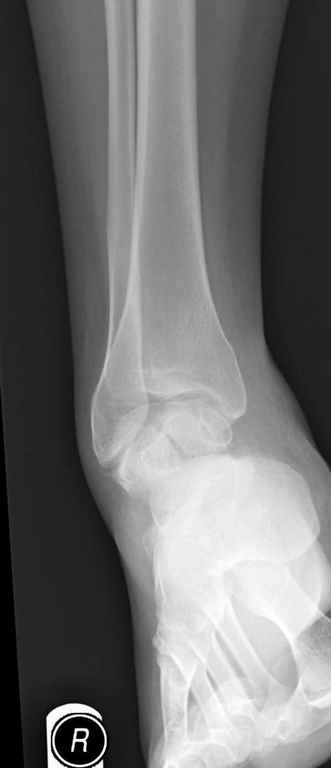

За пару недель насчитал 5 больных с переломом таранной кости, из них двое с двусторонним повреждением.

Из-за отека на стопе тактика лечения у всех была

одинаковая: временная наружная фиксация до спадения отека, при изолированных переломах они выписывались домой и через дней 7 госпитализировались на оперативное лечение.

Примеры на снимке...